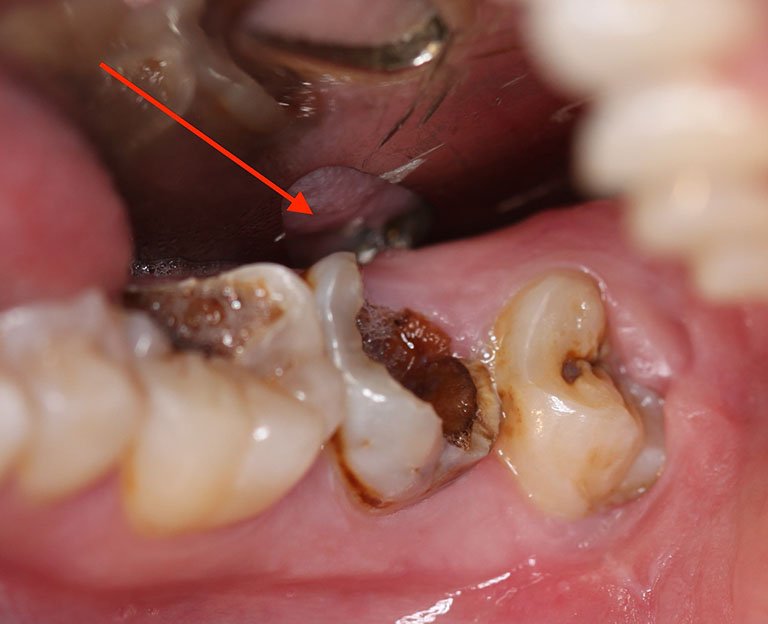

- Xuất hiện vết ố màu nâu hoặc đen: Khi tình trạng sâu răng nhẹ tiến triển, các đốm trắng dần chuyển thành vết ố màu nâu hoặc đen. Đây là dấu hiệu cho thấy men răng đã bị tổn thương nghiêm trọng hơn. Các vết ố này có thể tạo thành các lỗ nhỏ trên bề mặt răng.

- Sâu thân răng: Đây là dạng phổ biến nhất của sâu răng nhẹ. Vi khuẩn tấn công và phá hủy men răng ở bề mặt răng, tạo thành những lỗ nhỏ. Mặt nhai của răng thường dễ bị sâu nhất vì đây là nơi thức ăn dễ bị mắc kẹt.

- Nguy cơ nhiễm trùng: Nếu không điều trị, sâu răng nhẹ có thể tiến triển thành sâu răng nặng, dẫn đến viêm tủy răng, áp xe răng hoặc nhiễm trùng xương hàm.